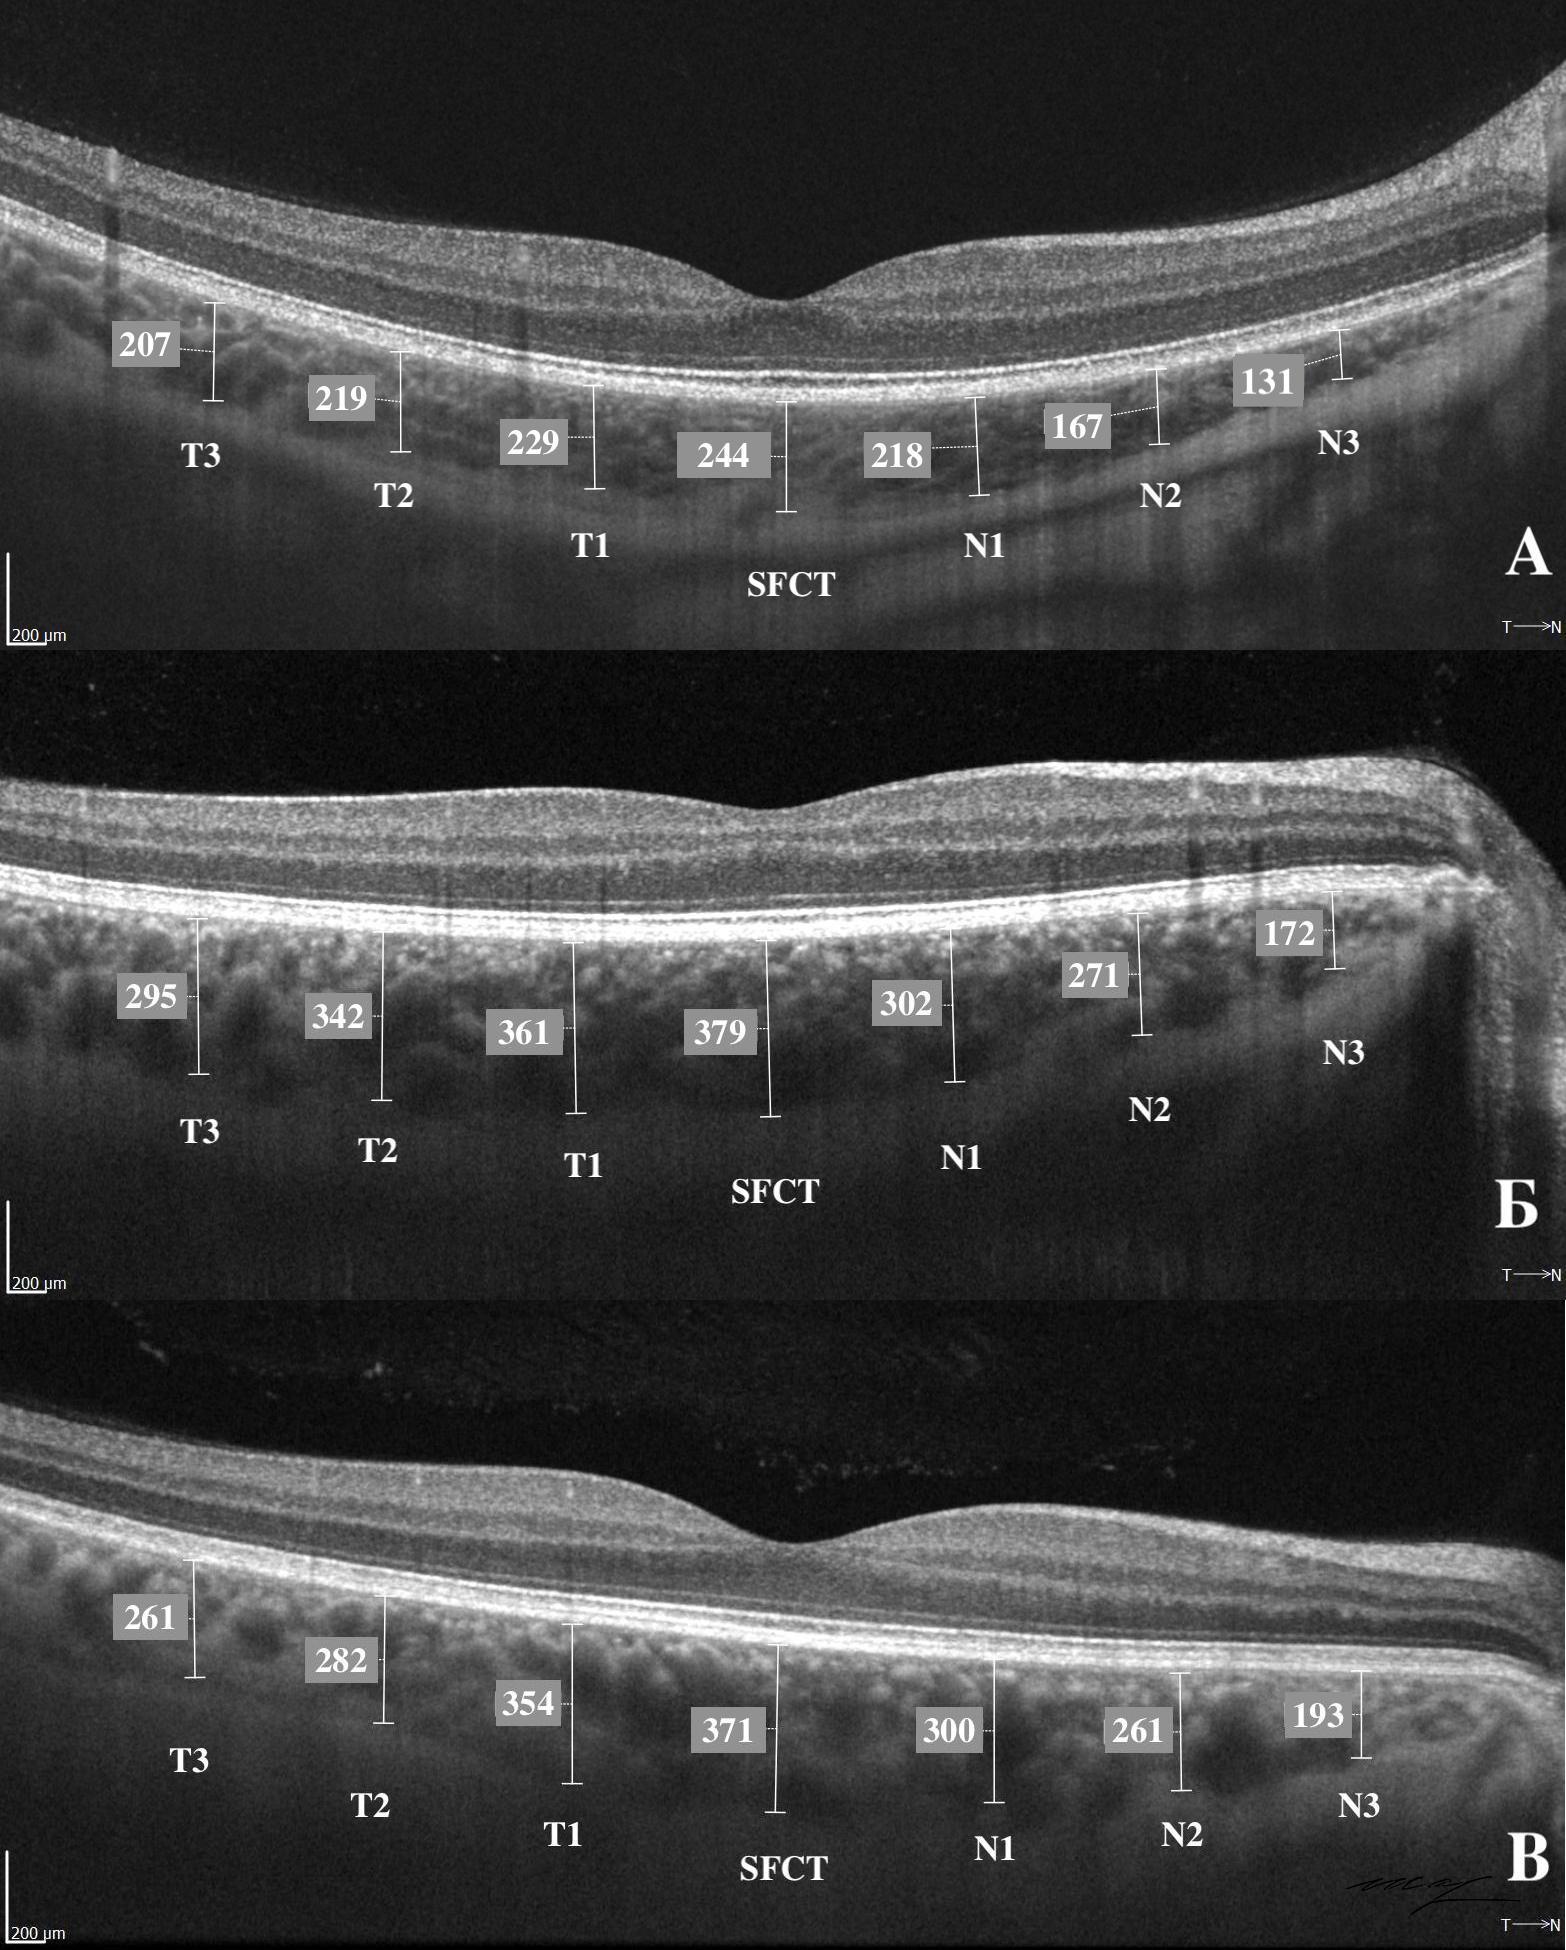

РЕЗУЛЬТАТЫ. ТХф при ПЗУ (341±59 мкм) и ППЗУ (340±51 мкм), была выше, чем в контроле (257,0±37,0 мкм, p<0,05). При ПЗУ и ППЗУ выявлены корреляции ТХф с возрастом, AL, LV, ICurv, IT750 (все p<0,05), а также установлены корреляции LV с возрастом, ВГД, ACD, ICurv, IT750, AOD500, AOD750, TISA500, TISA750 (все p<0,05). Только при ПЗУ отмечалась корреляция ТХф с ВГД (p=-0,476; p=0,008).

1. Рис. 1. Визуализация толщины хориоидеи в макуле на горизонтальном скане SS-OCT Revo NX130, «Optopol» | |